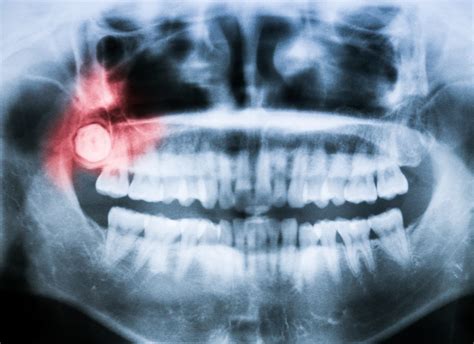

Once you suspect that your wisdom teeth are causing issues, a professional evaluation is non-negotiable. Dentists typically use panoramic X-rays to view the orientation and proximity of the teeth to your nerves and sinuses. If the teeth are impacted or causing damage to neighboring structures, extraction is usually the recommended course of action.